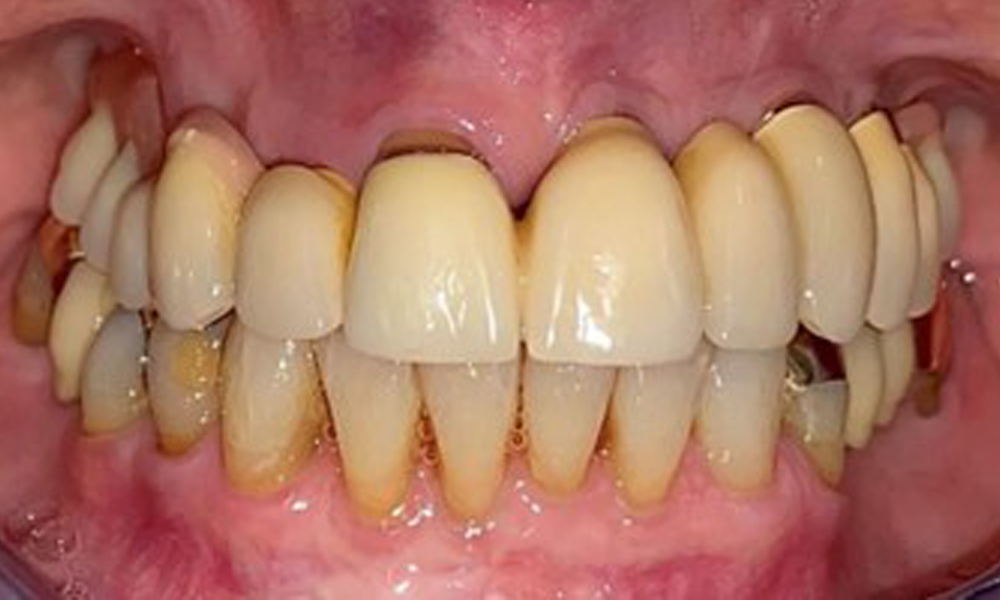

На пациентката е поставена комбинирана подвижна горночелюстна телескопична протеза преди повече от 25 години (фиг. 1, фиг. 2, фиг. 3) и тя е много доволна от протезите си. Пациентката има адекватна фиксирана протеза за долната челюст (фиг. 4).

Фронтален изглед с поставена горночелюстна протеза.

Фиг. 1: Фронтален изглед с поставена горночелюстна протеза.

Денталните открития са следните: Комбинирани снемаеми протези на импланти и телескопични протези, поддържани от зъби, на импланти 15, 13, 21, 23, 24, 25 и зъб 11 (фиг. 1, фиг. 2, фиг. 3). Пациентът е снабден с фиксирана долночелюстна протеза. Над зъби 37-34 и 45-47 бяха налични адекватни мостове (фиг. 4), краищата на коронките бяха интактни и нямаше активен кариес. Върху зъб 43 имаше композитна пломба с маргинална празнина. Имаше рецесия на долната гингива, която разкриваше от 1 до 3 mm от кореновата повърхност. Това се отнася и за 11.